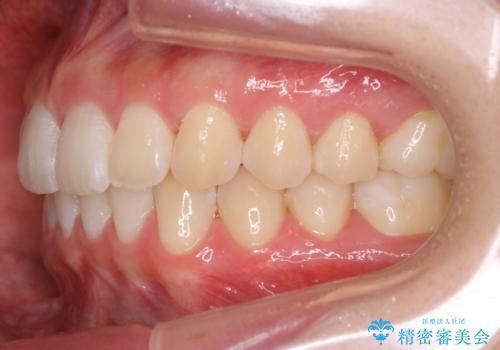

- 初診時、前歯のガタつきを主訴にご来院されました。

精密検査の結果奥歯の噛み合わせのズレからくる前歯のガタつきであることが分かり、患者様と相談した結果、全体をしっかりと治療することをご選択なさったので奥歯から動かして噛み合わせと見た目の両方を治す治療プランとなりました。

下顎の歯は幸いガタつきが少なかったため、下顎を基準とし構成する方針としました。